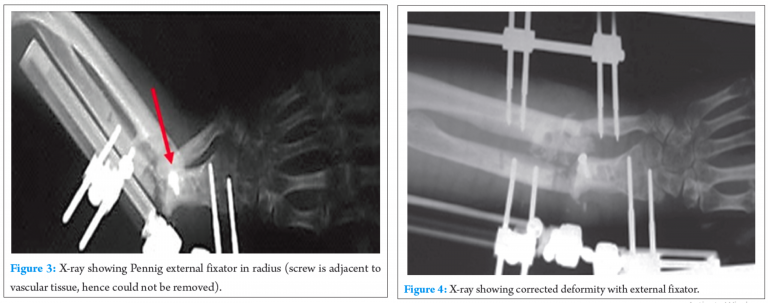

Implants were removed, except a screw, which was adherent to the adjacent vascular tissue. Pennig external fixator was applied on radius (Fig. 3), and universal mini external fixator was applied on ulna in another surgery. The deformity was corrected by gradually stretching (1 mm/day) the contracted soft tissue over a period of 6 weeks (Fig. 4). The neurovascular monitoring done clinically. Then, the external fixator was removed, once full correction was achieved. A long arm slab was applied in fully corrected position for 3 weeks.